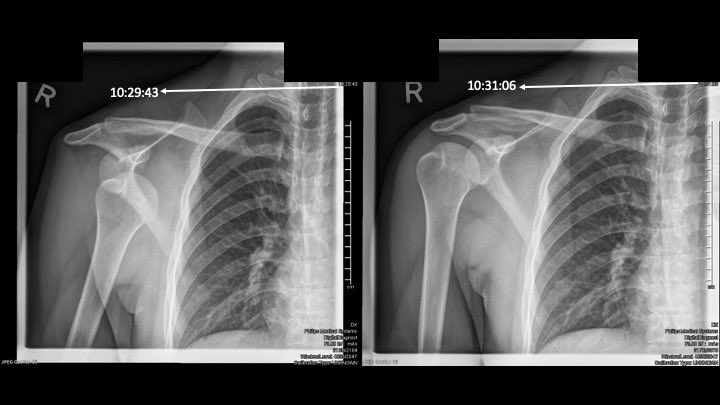

Thread: 1/3 Clinically anterior glenohumeral dislocation, confirmed by #POCUS within 5 min of arrival

2/3 Pain 10/10 to 0/10 within 5 min of interscalene block

3/3 X-ray was required for followup purposes. Patient walked to x-ray comfortably, and reduced in x-ray suite painlessly and effortlessly. ED LoS 40 min.